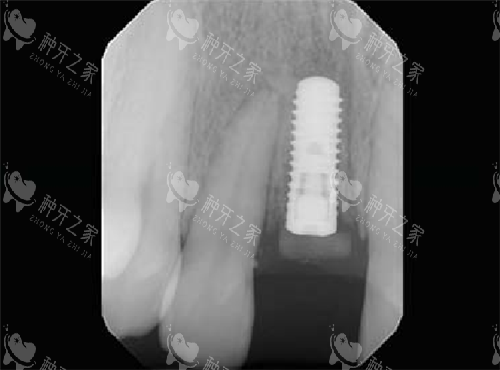

单颗种植:国产种植体3000元起,韩国登腾种植体4500元起,瑞士ITI种植体1.2万元起。

集采后价格直降50%,部分医院推出“种植+牙冠”套餐。

2024年集采前,进口种植体均价1.2万元;2025年集采后,同品牌价格降至6000元左右,降幅达50%。

评价3:45岁个体户赵叔的即刻种植

“后牙烂到只剩根,在龙华区人民医院当天拔当天种。

韩国登腾种植体+全瓷冠共6800元,比传统种植省了1个月等待期。

手术时听着音乐,40分钟就完成,下午就能吃面条。

医生提醒前3个月别用这侧嚼硬物,现在用着和真牙一样。”